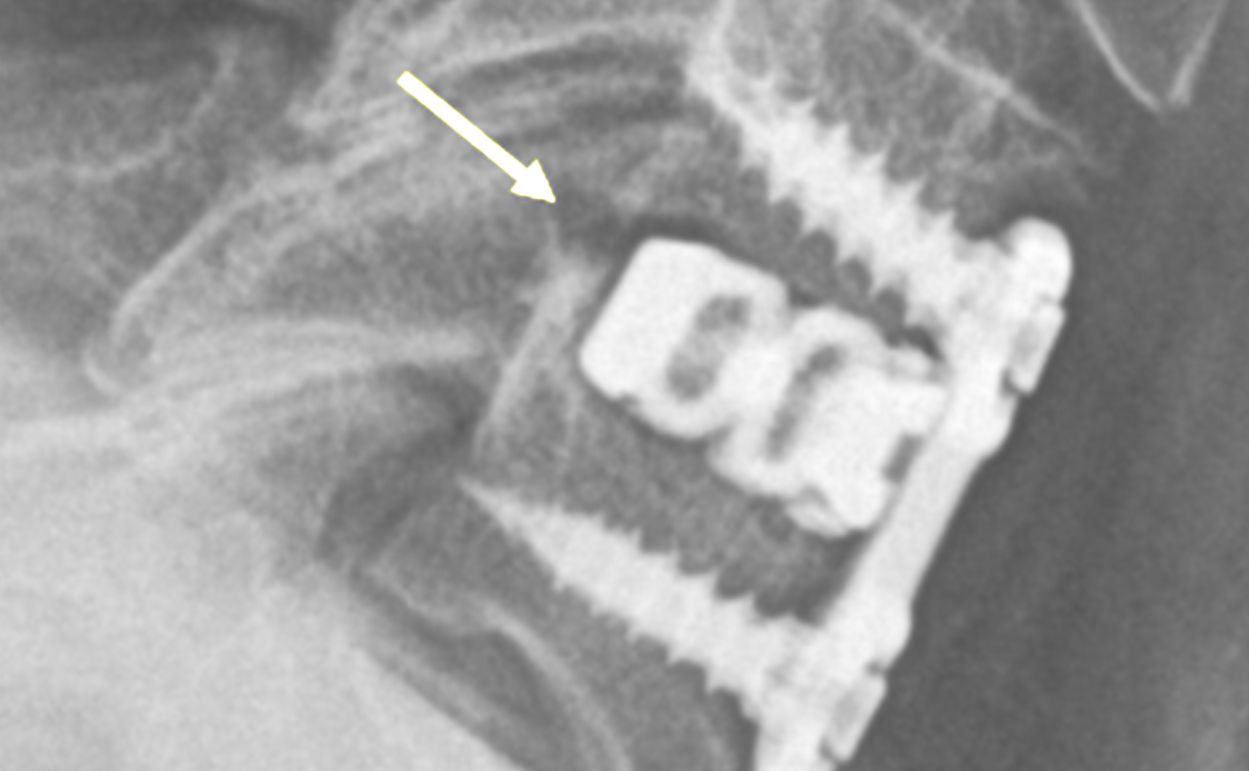

Arrow depicts baseline xray psuedoarthrosis posterior of cage.

CT scan imaging 16 months post op demonstrates osseous continuity posterior of cage.